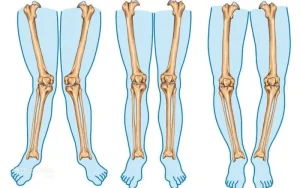

انحراف زانو به حالتی گفته میشود که محور طبیعی پاها از راستای استاندارد خود خارج میشود و زانوها در وضعیت غیرطبیعی قرار میگیرند. در حالت طبیعی، وقتی صاف میایستی، ران، زانو و مچ پا تقریباً در یک خط قرار میگیرند. این راستا باعث میشود وزن بدن بهطور متعادل روی مفاصل پخش شود. اما در انحراف زانو، این تعادل به هم میخورد.

از نظر علمی، انحراف زانو یعنی تغییر در زاویه بین استخوان ران و استخوان ساق. این تغییر زاویه باعث میشود فشار بیشتری به یک سمت مفصل زانو وارد شود. شاید در ابتدا بدن بتواند این فشار اضافی را جبران کند، اما در طول زمان، غضروف مفصل فرسوده میشود و درد و التهاب شروع میشود. نکته مهم اینجاست که زانو فقط یک مفصل جداگانه نیست؛ بلکه بخشی از یک زنجیره حرکتی است که از لگن شروع میشود و تا مچ پا ادامه دارد.

انحراف زانو شکلهای مختلفی دارد، اما دو نوع آن از همه شایعتر هستند: زانوی پرانتزی و زانوی ضربدری. هرکدام از این حالتها الگوی خاصی از فشار و عوارض را ایجاد میکنند و شناخت تفاوت آنها برای انتخاب روش درمان بسیار مهم است.

زانوی پرانتزی

در زانوی پرانتزی، وقتی فرد صاف میایستد و مچ پاها را به هم میچسباند، زانوها از هم فاصله دارند. پاها در این حالت شبیه پرانتز دیده میشوند. این نوع انحراف باعث میشود فشار بیشتری به قسمت داخلی مفصل زانو وارد شود. بهمرور، این فشار میتواند منجر به ساییدگی غضروف داخلی و آرتروز زودرس شود.

زانوی ضربدری

در زانوی ضربدری، برعکس حالت قبل، زانوها به هم نزدیک میشوند و مچ پاها از هم فاصله میگیرند. در این حالت، فشار اصلی روی قسمت خارجی مفصل زانو وارد میشود. این نوع انحراف میتواند باعث درد زانو، خستگی سریع پاها و حتی تغییر در نحوه راه رفتن شود.